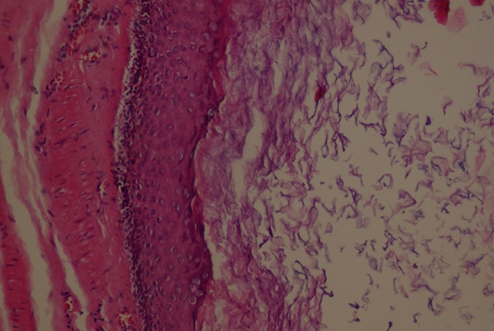

Ιστοπαθολογική εξέταση της επιδερμοειδούς κύστης (Ευγενική παραχώρηση Dr. V. Penopoulos)